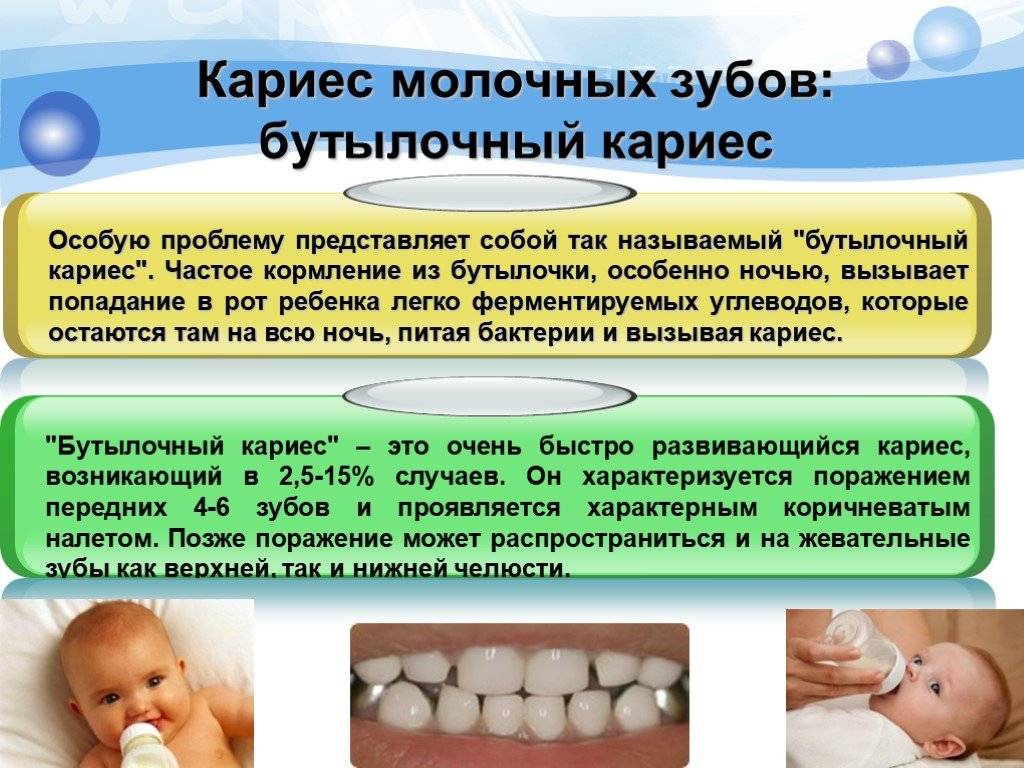

2) Неправильное питание – очень большое значение для возникновения кариеса в детском возрасте имеет неправильное питание. Главным образом речь идет об употребление большого количества сахаросодержащих продуктов и напитков. Мучные и крахмалистые продукты, все что содержит легкоусвояемые углеводы, мягкая пища, кислые и сладкие соки, а также газировка – все это приводит к быстрому появлению кариозных очагов (особенно в условиях недостаточной гигиены полости рта).

У маленьких детей наиболее неблагоприятное воздействие на зубы оказывают частые ночные кормления сладкими и кислыми продуктами (сладкая каша, сладкий чай, компот, сок, сладкий кефир или йогурт). В ночное время резко снижена секреция слюны, и поэтому уменьшаются ее возможности по нейтрализации кислот, по реминерализации эмали ионами кальция, а также нарушается процесс самоочищения полости рта, который в норме происходит за счет смывания пищевых остатков слюной.